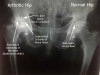

고관절의 AP, lateral view X-ray 검사를 합니다. 전형적인 이상소견은 관절간격 협소, 골극, 연골하 낭종형성, 연골하 경화증 소견입니다.

X-ray : 퇴행성 고관절염(Osteoarthritis of the hip)